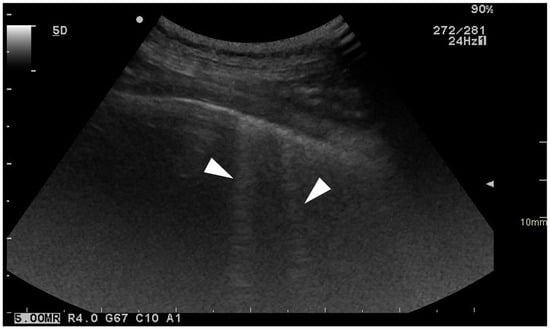

Cover Story (view full-size image): Lumbosacral radiculopathy is a frequent cause of back pain in dogs and humans, often associated with intervertebral disc herniation or foraminal stenosis. In medicine, transforaminal epidural injections are widely used to deliver therapeutic agents near affected spinal nerves. This study evaluated an ultrasound- and fluoroscopy-guided technique for lumbosacral foraminal injections in canine cadavers, assessing injectate distribution through fluoroscopy, computed tomography, and anatomical dissections to determine its precision and potential clinical application. View this paper